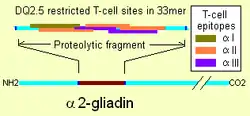

Membrane leaking permits peptides of gliadin that stimulate two levels of the immune response: the innate response, and the adaptive (T-helper cell-mediated) response. One protease-resistant peptide from α-gliadin contains a region that stimulates lymphocytes and results in the release of interleukin-15. This innate response to gliadin results in immune-system signalling that attracts inflammatory cells and increases the release of inflammatory chemicals.[28] The strongest and most common adaptive response to gliadin is directed toward an α2-gliadin fragment of 33 amino acids in length.[28]

The response to the 33mer occurs in most coeliacs who have a DQ2 isoform. This peptide, when altered by intestinal transglutaminase, has a high density of overlapping T-cell epitopes. This increases the likelihood that the DQ2 isoform will bind, and stay bound to, peptide when recognised by T-cells.[75] Gliadin in wheat is the best-understood member of this family, but other prolamins exist, and hordein (from barley), secalin (from rye), and avenin (from oats) may contribute to coeliac disease.[28][49][76] Avenin's toxicity in people with coeliac disease depends on the oat cultivar consumed, as prolamin genes, protein amino acid sequences, and the immunoreactivities of toxic prolamins vary among oat varieties.[20]